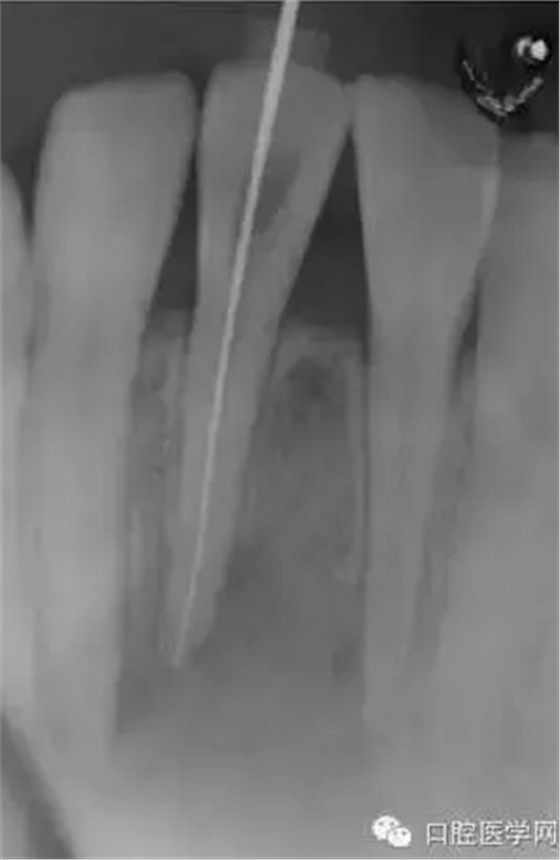

(圖 2) 根管長度測定

就診當(dāng)日進(jìn)行了開髓,測量根管長度及根管成形。開髓時(shí)釋放出嚴(yán)重的惡臭,而且可以看到大量膿液通過根管流出來。當(dāng)日于唇側(cè)腫脹部位的最下端進(jìn)行了半月形切口,使膿液從切口處流出,通過根管和切口,使用大量地生理鹽水清洗根尖病灶部位。當(dāng)天根管成形后,為防止食物塞入根管內(nèi),并便于膿液或氣體的排出,使用棉球封住根管口。